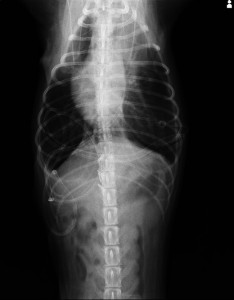

再発時のレントゲンです。クリップが外れているなどの所見はありませんでした